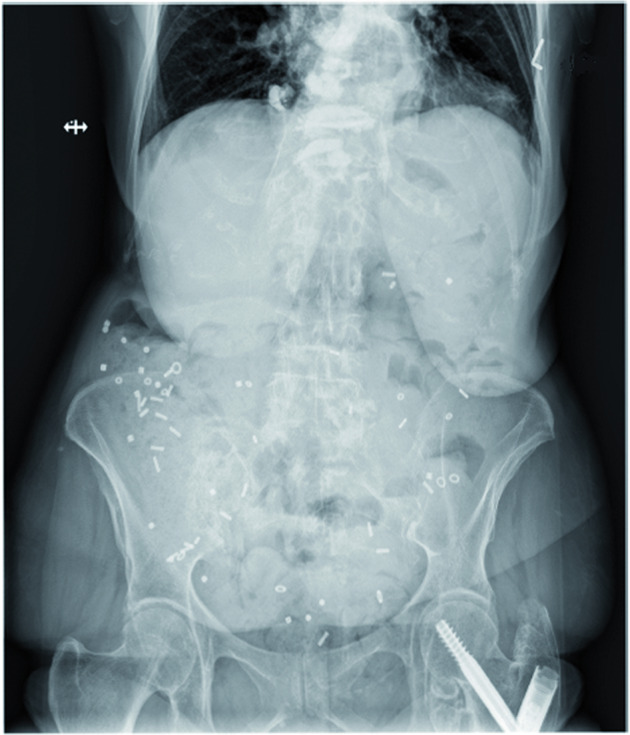

Aproximadamente la mitad de los pacientes con COVID-19 eliminan el ARN fecal en la semana posterior a la infección. El 4% de los pacientes con COVID-19 arrojan ARN viral fecal 10 meses después del diagnóstico. La presencia de ARN de SARS-CoV-2 fecal se asocia con síntomas gastrointestinales. Es probable que el SARS-CoV-2 infecte el tejido gastrointestinal. Med (N Y), 12 de abril de 2022

Revisamos el conocimiento actual sobre la fisiopatología, la fisiopatología, el diagnóstico y el tratamiento del tracto gastrointestinal en la enfermedad de Parkinson  y brindamos recomendaciones para el manejo en la práctica diaria. npj Parkinson's Disease, 22 de marzo de 2022